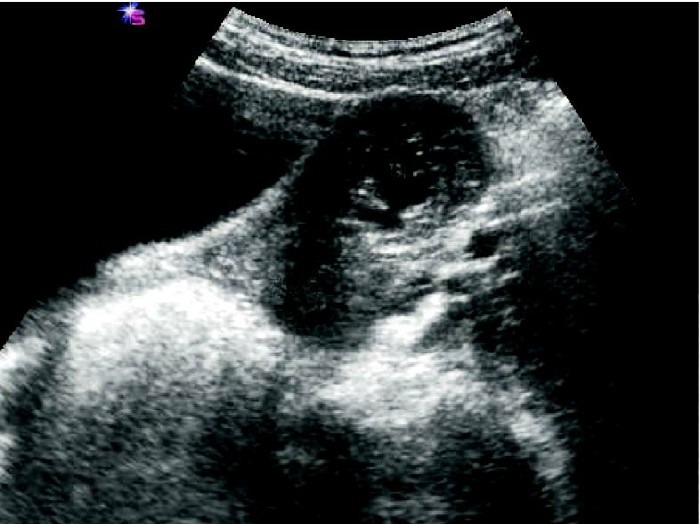

患者,女,25 岁。停经56 天,尿HCG(+),外院人工流产失败转来本院。经阴道超声检查显示:子宫横切面,宫腔内未见胚囊,右宫角突起肌层内见胚囊、胚芽、胎心,胚囊与宫腔不相通。

超声诊断:右宫角肌层内见胚囊、胚芽、胎心,间质部妊娠。

手术病理:(右)输卵管间质部妊娠。